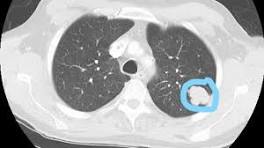

| CORA Partners with St. Charles Cancer Center to Provide Low-Dose CT Lung Screenings Lung cancer is the leading cause of cancer death in the United States, but if diagnosed early it is much easier to treat. Low-dose CT (LDCT) is the only ...

| Media outlets highlight study looking at how the pandemic impacted lung cancer screening It's a program that uses CT scans to find lung nodules and lung cancers early," he says. "It's an important program because it reduces cancer mortality ...

| |||||||